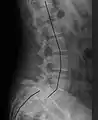

X-ray of the lateral lumbar spine with a grade III anterolisthesis at the L5-S1 level | |

Spondylolisthesis is the displacement of one spinal vertebra compared to another. While some medical dictionaries define spondylolisthesis specifically as the forward or anterior displacement of a vertebra over the vertebra inferior to it (or the sacrum),[1][2] it is often defined in medical textbooks as displacement in any direction.[3][4] Spondylolisthesis is graded based upon the degree of slippage of one vertebral body relative to the subsequent adjacent vertebral body.[5] Spondylolisthesis is classified as one of the six major etiologies: degenerative, traumatic, dysplastic, isthmic, pathologic, or post-surgical.[6] Spondylolisthesis most commonly occurs in the lumbar spine, primarily at the L5-S1 level, with the L5 vertebral body anteriorly translating over the S1 vertebral body.[6]

Classification by degree of the slippage, as measured as percentage of the width of the vertebral body:[14] Grade I spondylolisthesis accounts for approximately 75% of all cases.[6]

- Grade I: 0–25%

- Grade II: 25–50%

- Grade III: 50–75%

- Grade IV: 75–100%

- Grade V: greater than 100%